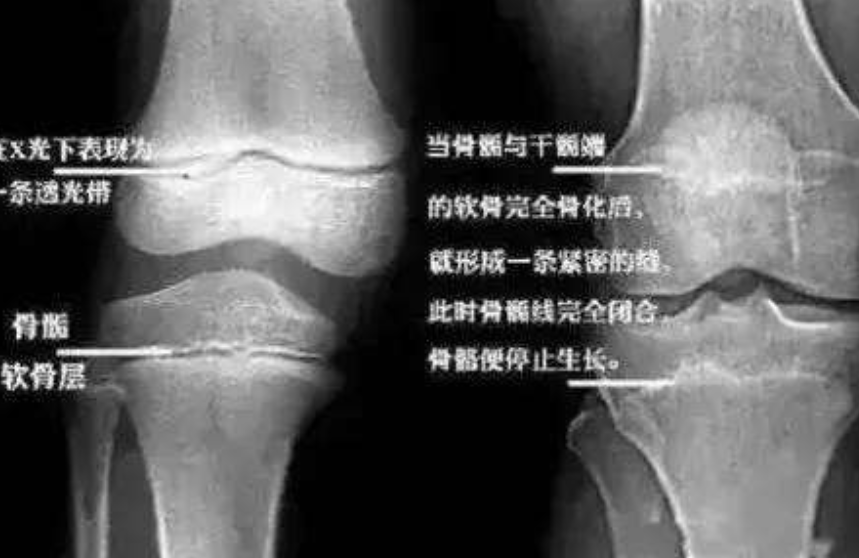

在招飞工作开始前半学期,李亚诺父母就带他到医院检查骨骼发育情况,骨骼科的医生通过检查骨骺线的开闭情况来判断一个人还能不能长高。这是由于人体身高的生长主要依靠人体的骨骺末端生长板细胞增殖分化来实现的。也就是说如果这条线闭合了,就证明骨头末端已经不存在生长细胞了,长高自然也是无稽之谈。

是啊,那时的李亚诺和自己的梦想与美好的前程,只差区区3cm。医生叹了口气,虽心怀不忍还是对这一家三口说道:“从片子来看确实已经完全愈合了,按照现在的医学技术已经没有办法长高了,其实人生不只当飞行员这一条路,趁着时间还来得及,不如回去好好复习文化课,考一所好的大学。”医生的话非常在理,可惜李亚诺并没有听进去……